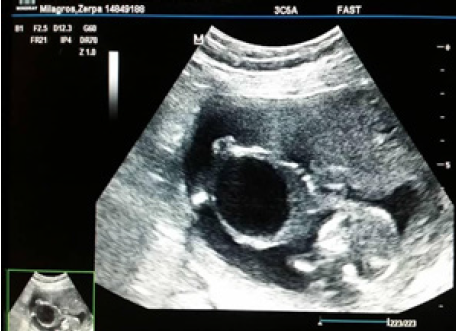

Se trata de paciente femenina de 39 años, sin antecedentes familiares, personales y patológicos conocidos, V gestas, II partos, I cesárea, I aborto, FUR incierta, quien inicia control prenatal durante el primer trimestre del embarazo. El estudio ultrasonográfico reporta imagen anecoica, redondeada, que ocupa pelvis y abdomen fetal (Figura 1).